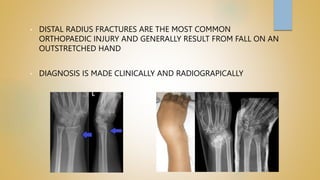

• DISTAL RADIUS FRACTURES ARE THE MOST COMMON

ORTHOPAEDIC INJURY AND GENERALLY RESULT FROM FALL ON AN

OUTSTRETCHED HAND

• DIAGNOSIS IS MADE CLINICALLY AND RADIOGRAPICALLY